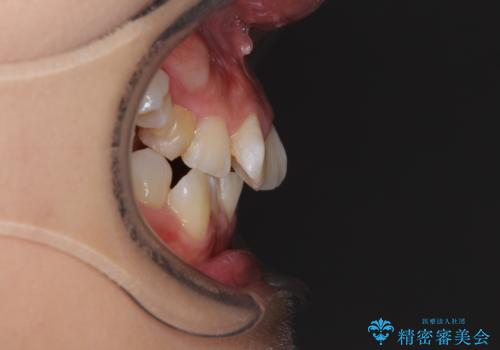

- 前歯のでこぼこと乳歯が残るほどの八重歯を気にして来院された患者様です。

非抜歯にてワイヤー矯正にて治療することとしました。(ただし、親知らずと乳歯は抜歯)

犬歯は歯根が太く長いため、移動には時間を要します。しかし、犬歯は機能面から考えて残すことを選択したいため、長期間をかけて治療を行うこととしました。